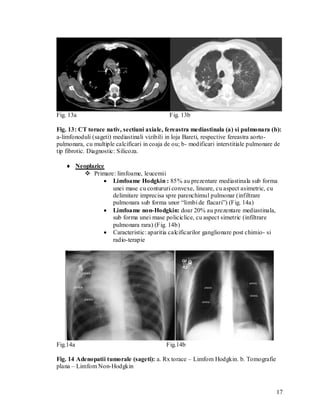

Fig. 13a                                     Fig. 13b

Fig. 13: CT torace nativ, sectiuni axiale, fereastra mediastinala (a) si pulmonara (b):

a-limfonoduli (sageti) mediastinali vizibili in loja Bareti, respective fereastra aorto-

pulmonara, cu multiple calcificari in coaja de ou; b- modificari interstitiale pulmonare de

tip fibrotic. Diagnostic: Silicoza.